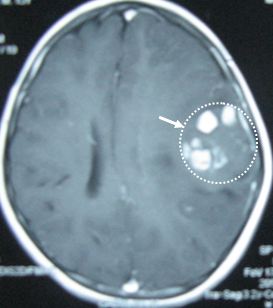

Chụp MRI sọ não phát hiện tại thuỳ thái dương trái có 3 khối u kích thước các khối 1,5 x 1,5 cm, ngoài ra còn có các u kích thước nhỏ xung quanh. Hình ảnh MRI gợi ý đến hình ảnh u Lympho não hơn là di căn não. Bệnh nhân được chỉ định mở sọ não lấy u làm giải phẫu bệnh nhưng bệnh nhân đã từ chối phẫu thuật.

Hình ảnh chụp MRI sọ não trước và sau điều trị

Bệnh nhân được tiến hành điều trị hoá chất phác đồ CHOP  8 đợt và tiêm Methotrexat nội tuỷ, kết quả u sọ não tan hoàn toàn. Đến nay, bệnh nhân đã được ra viện 10 tháng. Hiện tại vẫn khoẻ mạnh, chụp MRI sọ não không phát hiện ra khối u.